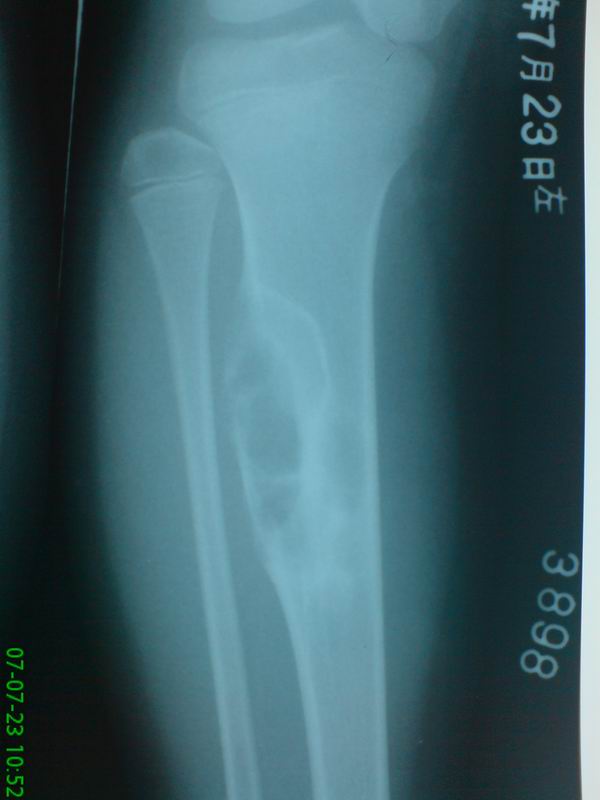

标题: PED0280:女性,10岁,左小腿无诱因疼痛,一般状况良好,无发热乏 [打印本页]

标题: PED0280:女性,10岁,左小腿无诱因疼痛,一般状况良好,无发热乏

胫骨中上段多房囊肿,呈蜂窝状向外膨胀,囊内含有粗细不等的房间隔。考虑动脉瘤样骨囊肿!

胫骨骨干增粗,骨皮质呈膨张性改变。髓腔扩大,其内有多个圆性低密度影,且有长短不一的骨瘠影。邻近骨质硬化。外围骨皮质部分消失。考虑软骨粘液样纤维瘤可能性大。

胫骨中上段多房囊肿,呈蜂窝状向外膨胀,囊内含有粗细不等的房间隔,偏心性生长。考虑良性骨肿瘤----1软骨粘液性纤维瘤。2骨化或非骨化性纤维瘤。